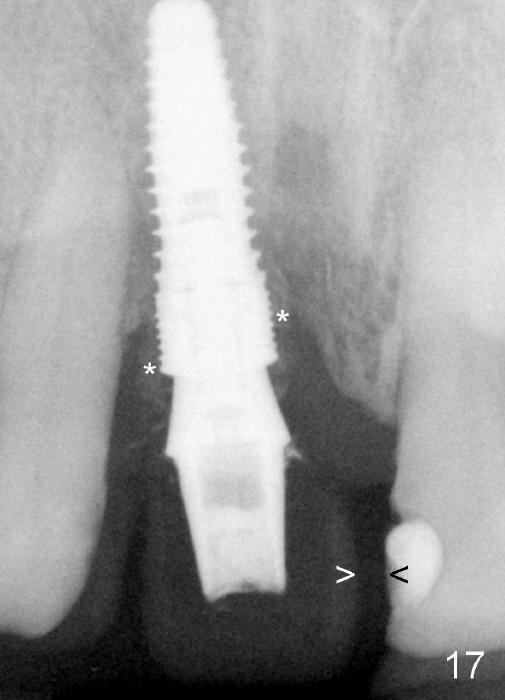

Four-month follow up shows that bone graft from the tuberosity appears to have healed with the implant microthreads (Fig.17 *); there is a diastema between #8 and 9 (arrowheads). Before removal of the provisionals of #7 and 8 for final impression, new composite is added to the mesial surface of #9 as the first step of closure of the diastema (Fig.18 <).